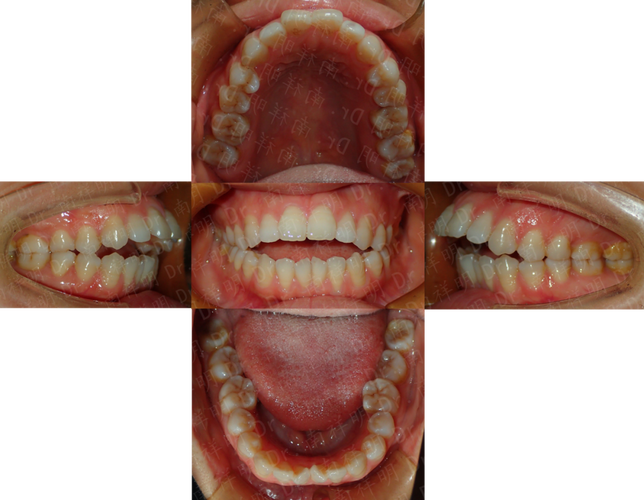

成人正畸的方案设计需兼顾“牙齿排齐”与“面部美学”,北大口腔医院尤为注重个性化方案的定制,医生会通过全面的面部分析、口内检查、功能评估及影像学检查,结合患者的职业、年龄、美观需求及治疗预期,制定差异化的矫治策略,对于前牙深覆合、深覆盖且伴有面部凹陷的患者,可能需要通过正畸-正颌联合治疗改善咬合关系与面部轮廓;对于轻度牙列拥挤且对美观要求极高的患者,隐形矫治或舌侧矫治则成为首选,既能实现牙齿移动,又能最大限度满足美观需求,在方案沟通阶段,医生会利用3D动态模拟技术,向患者直观展示牙齿移动过程及预期效果,让患者充分参与治疗决策,提升治疗依从性。

成人正畸的矫治器选择多样,每种类型均有其适应人群与优缺点,患者可根据自身需求与医生建议选择合适的方式,传统金属托槽矫治器因其强度高、适用范围广、价格相对亲民,仍是复杂病例的首选,尤其是对于需要大幅度牙齿移动、扭转或压低的患者;陶瓷托槽矫治器托槽颜色与牙齿相近,美观性优于金属托槽,适合对美观有一定要求的患者,但需注意避免食用色素较深的食物以防染色;隐形矫治器(如隐适美、时代天使等)凭借其透明、可摘戴、舒适度高、便于清洁的优势,成为近年来成人正畸的热门选择,尤其适合轻度至中度牙列不齐、希望缩短复诊时间的患者,但需患者具备良好的自律性,确保每日佩戴时间不少于20小时;舌侧矫治器将托槽粘贴于牙齿舌侧面,完全隐形,对美观要求极致的患者具有吸引力,但技术难度高、费用昂贵,且初期对发音、口腔舒适度的影响较大,需医生具备丰富的临床经验,以下是常见矫治器类型的对比参考:

成人正畸的治疗流程通常分为以下几个阶段:初诊检查与资料收集、方案设计与沟通、矫治器佩戴与调整、保持器佩戴与维护,初诊阶段,医生会进行全面的口腔检查,包括牙齿排列、咬合关系、牙周状况、颞下颌关节功能等,并拍摄曲面断层片、头颅侧位片、CBCT及面部照片,收集完整数据;方案设计阶段,医生结合检查结果与患者需求,制定详细的矫治计划,并通过3D模拟演示治疗效果,与患者确认后进入矫治阶段;矫治器佩戴后,患者需定期复诊(通常为4-8周一次),医生会检查牙齿移动情况,调整矫治力,确保治疗进度;当牙齿排齐、咬合关系稳定后,拆除矫治器,佩戴保持器以防止复发,保持器通常需全天佩戴6-12个月,之后逐渐减少夜间佩戴时间。

成人正畸的注意事项与青少年正畸存在明显差异,口腔健康预处理是关键,成年患者常伴有牙周炎、牙龈炎、龋齿等问题,需先进行牙周治疗、补牙等基础治疗,待口腔健康状况稳定后再开始正畸,否则可能加重牙周损伤,治疗周期相对较长,成人牙槽骨改建速度较慢,平均治疗时间为1.5-3年,复杂病例可能需要更长时间,患者需有充分的心理准备,口腔卫生维护尤为重要,佩戴矫治器后食物易嵌塞,若清洁不到位易导致龋齿、牙周炎,因此需使用正畸专用牙刷、牙缝刷、冲牙器等工具,每日彻底清洁牙齿及矫治器,成人正畸需兼顾面部美学与功能平衡,医生会根据患者的面部比例、微笑曲线等设计牙齿移动方向,避免“排齐但不好看”的情况发生。